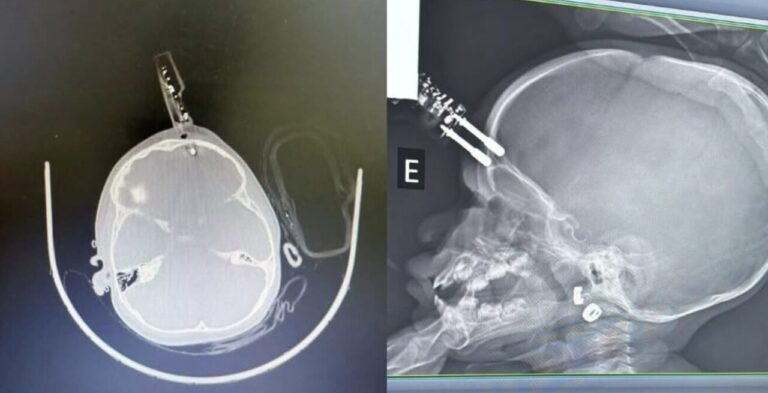

Uma menina de apenas 1 ano precisou ser operada com urgência após cair da cama com um carregador de celular nas mãos, em Divinópolis, Minas Gerais. O objeto ficou cravado na testa da criança, atravessando o osso frontal e atingindo o tecido cerebral. Apesar da gravidade do trauma, a menina está internada, em observação, e até o momento não apresenta sinais de sequelas neurológicas, segundo o neurocirurgião responsável, Bruno Castro.

O acidente ocorreu enquanto a mãe estava no banheiro. Segundo o médico, a principal hipótese é que a criança segurava o carregador no momento da queda, o que provocou o impacto com perfuração. O procedimento cirúrgico foi imediato e envolveu a remoção do objeto, limpeza da área afetada e reconstrução da região atingida. A menina está sendo tratada com antibióticos para evitar infecções, já que a introdução de um objeto contaminado no sistema nervoso pode causar doenças graves como meningite.